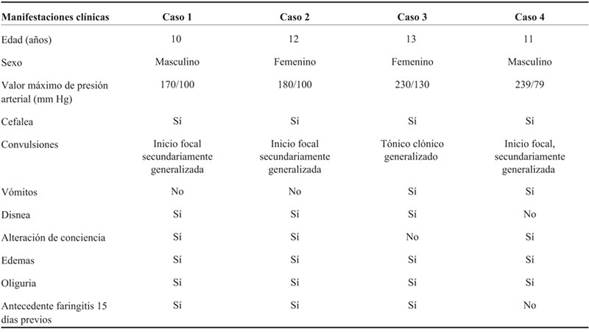

La mediana de PA sistólica (PAS) fue 200 mmHg (rango 170-239) y de PA diastólica (PAD) 100 mmHg (rango 79-130). El antecedente de faringitis se presentó en tres de los cuatro niños. Los cuatro pacientes cumplían con los criterios diagnósticos de glomerulonefritis difusa aguda posestreptocócica (proteinuria, insuficiencia renal reversible, disminución de C3 y aumento del AELO). El caso 1 requirió biopsia renal por evolución inhabitual de las cifras de azoemia y creatininemia, que evidenció histología compatible con glomerulonefritis difusa aguda.

Ningún paciente presentó secuelas neurológicas al alta. En tres pacientes se realizó control imagenológico con RM luego de los 15 días del alta, evidenciando reversión completa de las alteraciones a nivel de sustancia blanca (Tabla 2).